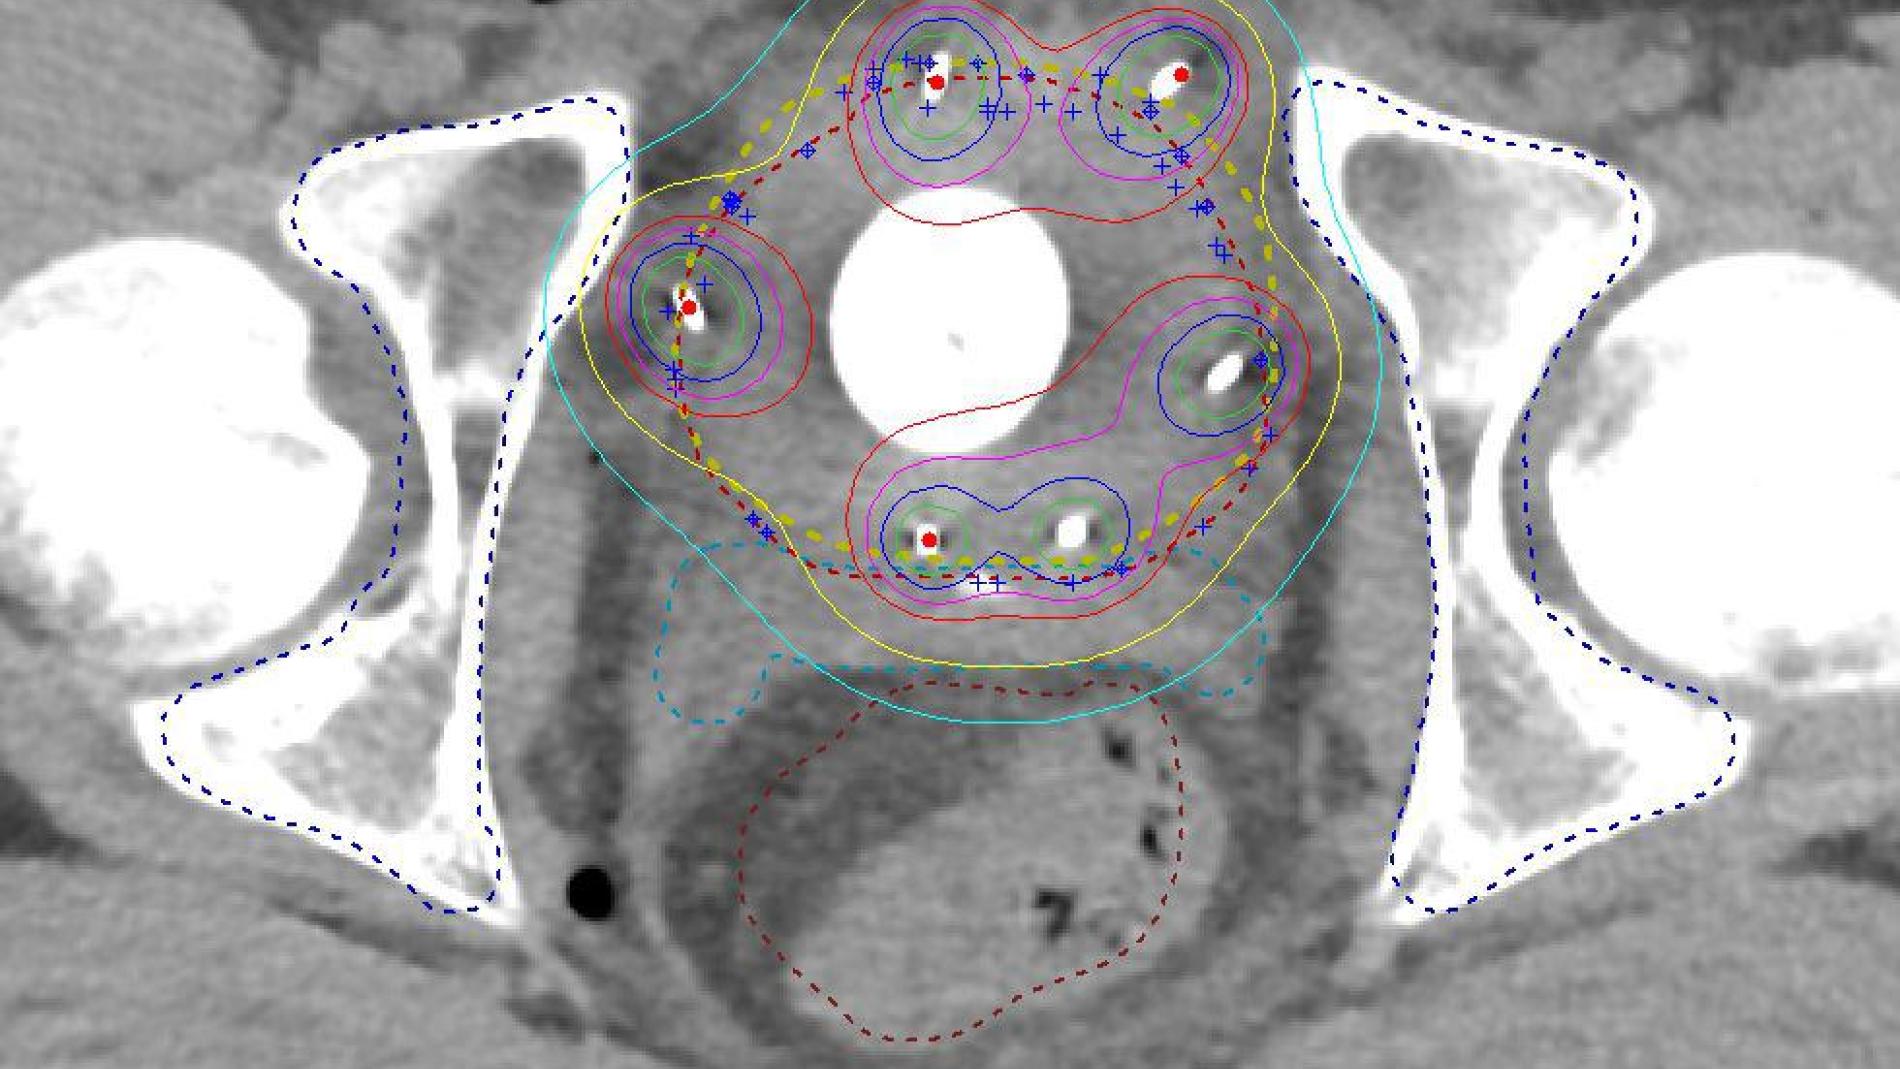

Ara, un equip de professionals de l’Hospital Universitari Vall d’Hebron, liderat per la Dra. Gabriela Guillen, del Servei de Cirurgia Pediàtrica, s’ha format en aquests centres per implementar aquesta tècnica de manera que estigui disponible a tots els centres d'Espanya mitjançant les xarxes de referència anomenades CSUR. La Dra. Marta Martos, adjunta de Cirurgia Pediàtrica, va aprofitar una de les estades formatives a centres internacionals per aprendre la tècnica a l’hospital Bicêtre de París. La braquiteràpia consisteix en la implantació quirúrgica de cànules molt fines dins del tumor, a través de les quals s’administra la radiació de manera localitzada, reduint al mínim el dany als teixits sans. “Aquesta tècnica s’ha demostrat més eficaç que altres formes de radioteràpia en aquestes localitzacions anatòmiques tan especials, inclosa la protonteràpia, i ofereix excel·lents  taxes de curació amb menys seqüeles”, destaca la Dra. Gabriela Guillén. La braquiteràpia redueix l'exposició dels teixits sans a la radiació, un aspecte fonamental en nens en creixement. “A més, en permet l’aplicació d’una dosi localitzada més alta i disminueix significativament el risc de desenvolupar tumors malignes secundaris induïts per la radiació”, precisa.

El procés es realitza en dues fases: primer, els cirurgians pediàtrics de Vall d’Hebron intervenen el pacient i revisen el tumor i l’equip de braquiteràpia de l’ICO implanta els tubs o aplicadors a la zona del tumor. I per rebre la radiació a través d’aquests tubs de manera controlada i precisa, es va i ve de l’ICO a la seva seu de l’Hospitalet de Llobregat. Durant uns cinc dies, l’infant es desplaça entre els dos hospitals en ambulància del SEM acompanyat de la família i un dels professionals de Vall d’Hebron per completar el tractament, que es realitza en dues sessions diàries separades per sis hores. Finalitzat el procediment, torna al seu hospital d’origen per continuar amb el seguiment.